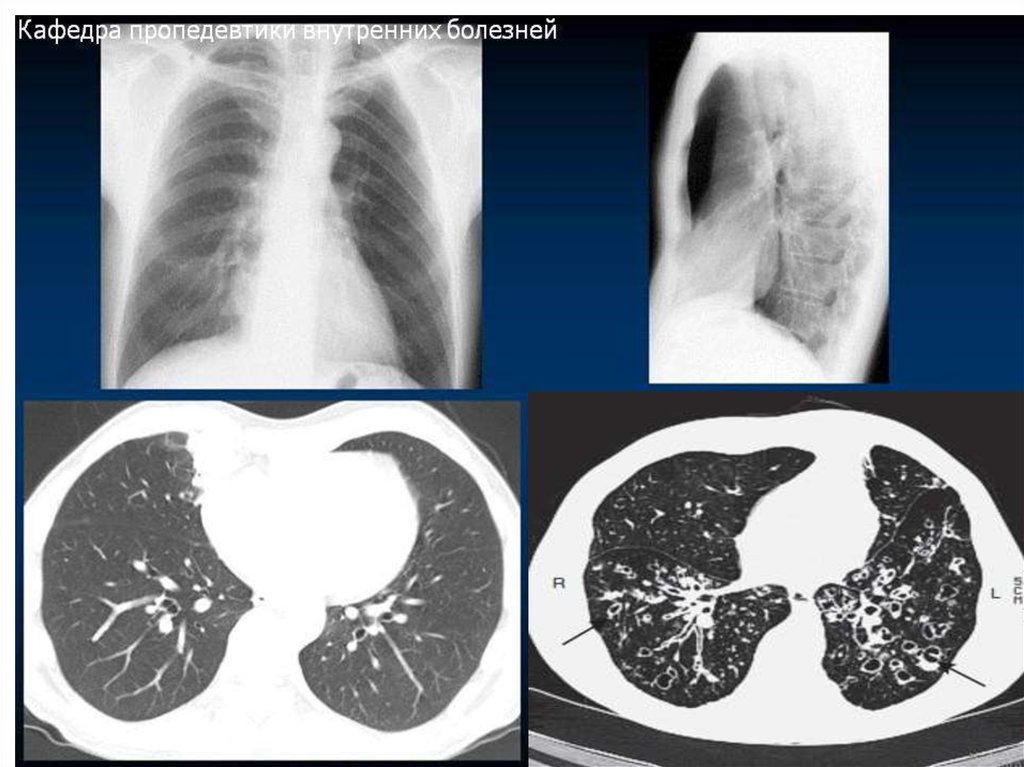

21. Рентгенологическое исследование грудной клетки

• В прямой проекции:

- состояние легочных

полей, сердца,

средостения, сосудов и

грудной клетки

• В боковой проекции:

- патология позади

сердца

- патология глубоко в

диафрагмальном синусе

22. Томография легких (рентгенологическая, компьютерная)

Локализация и размер повреждения легких

Участки кальцификации

Участки образования полостей

Определение степени и типа эмфиземы

легких

• Проводится при подозрении на рак легких

(чрескожная тонкоигольная биопсия)

• Диагностика ТЭЛА (КТ с ангиографией ЛА)